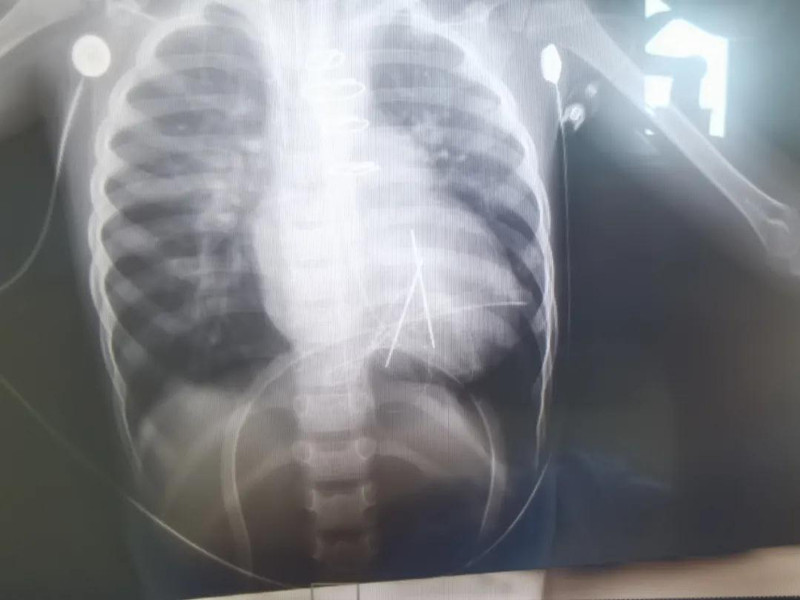

3月13日,医院专家团队为馨馨手术。术中安装了临时起搏导线,以预防术后出现心律失常。很幸运,手术一切顺利。术后继续给予馨馨呼吸机支持通气和使用强心利尿药物,改善心功能。目前馨馨恢复非常好。如果不出意外,经过3个月到半年的恢复,馨馨的心脏就能恢复到正常状态了。